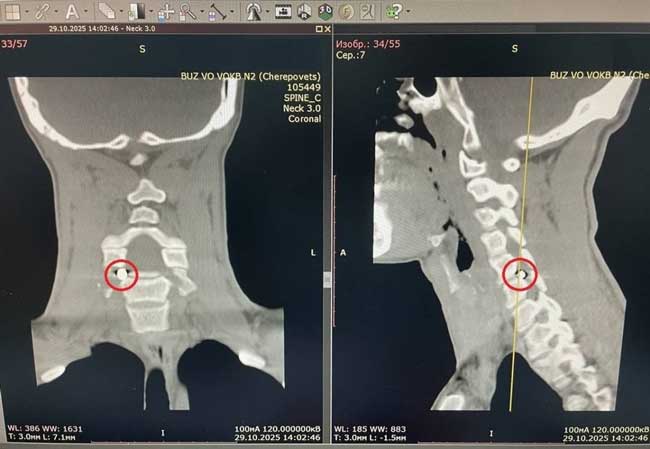

При проведении спиральной компьютерной томографии врачи выявили осколок размером 5×4 мм, расположенный в позвоночном канале. Фрагмент снаряда сдавливал корешок спинного мозга, что приводило к выраженной боли, иррадиирующей в руку, а также к онемению и снижению силы кисти.